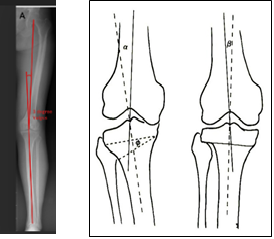

Tibio-femoral angle

It is the angle between mechanical axes of femur and tibia, done in weight bearing, full length lower limb (LL) x-ray A/P view. The angle can`t measure accurately until a child is able to stand by self. The first line is illustrated from the center of femoral head to tip of the femoral intercondylar notch and another from midpoint of tibial inter-spinous line to the tibial mid-plafond. The tibio-femoral angle is useful to quantify the degree of valgus or varus alignment at knee, also after total knee replacement. Varus knee is physiological from birth to 24 months of age and then valgus until 7 years is normal. 1-1.50 varus is normal in adult and in healthy person it can be 10 valgus and 3.20 varus.19

Tibio-femoral angle 30 valgus in normal knee.

Tibio-femoral angle before & after deformity correction.

CORA (center of rotation of angulation)

It is a method of both mechanical and anatomical axis planning based on joint orientation and a system of deformity analysis for the purpose of corrective osteotomy and hardware fixation.

Mechanical axis: It is the straight line that connects the center points of upper and lower joints in frontal or sagittal plane, through which the force of axial mechanical load pass of during in static weight bearing.

On anteroposterior (A/P) evaluation, in case of tibia the mechanical and anatomical axis coincides each other, but in femur those are separate. The mechanical axis in femur goes from the center of femoral head to knee joint center. Concerning for the lower limb, it extends from the center of femoral head to the center of ankle joint and normally pass through the center of knee joint. The mechanical axis is always a straight line in both frontal and sagittal plane, but the anatomical axis may be straight in frontal plane but curved in sagittal plane as in femur.17

In deformed tibia, CORA determination is so simple, because both mechanical and anatomical axes are amalgamate and goes through center of tibial diaphysis. The anatomical axis of each segment of deformed tibia drawn on x-ray, the lines will intersect and the acute angle between the lines is CORA.